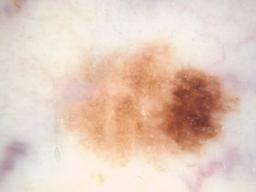

{

"age_approx": 45,

"anatom_site_general": "anterior torso",

"clin_size_long_diam_mm": "4.50",

"concomitant_biopsy": true,

"diagnosis_1": "Malignant",

"diagnosis_2": "Malignant melanocytic proliferations (Melanoma)",

"diagnosis_3": "Melanoma in situ",

"diagnosis_confirm_type": "histopathology",

"family_hx_mm": false,

"image_type": "dermoscopic",

"melanocytic": true,

"personal_hx_mm": false,

"sex": "female"

}